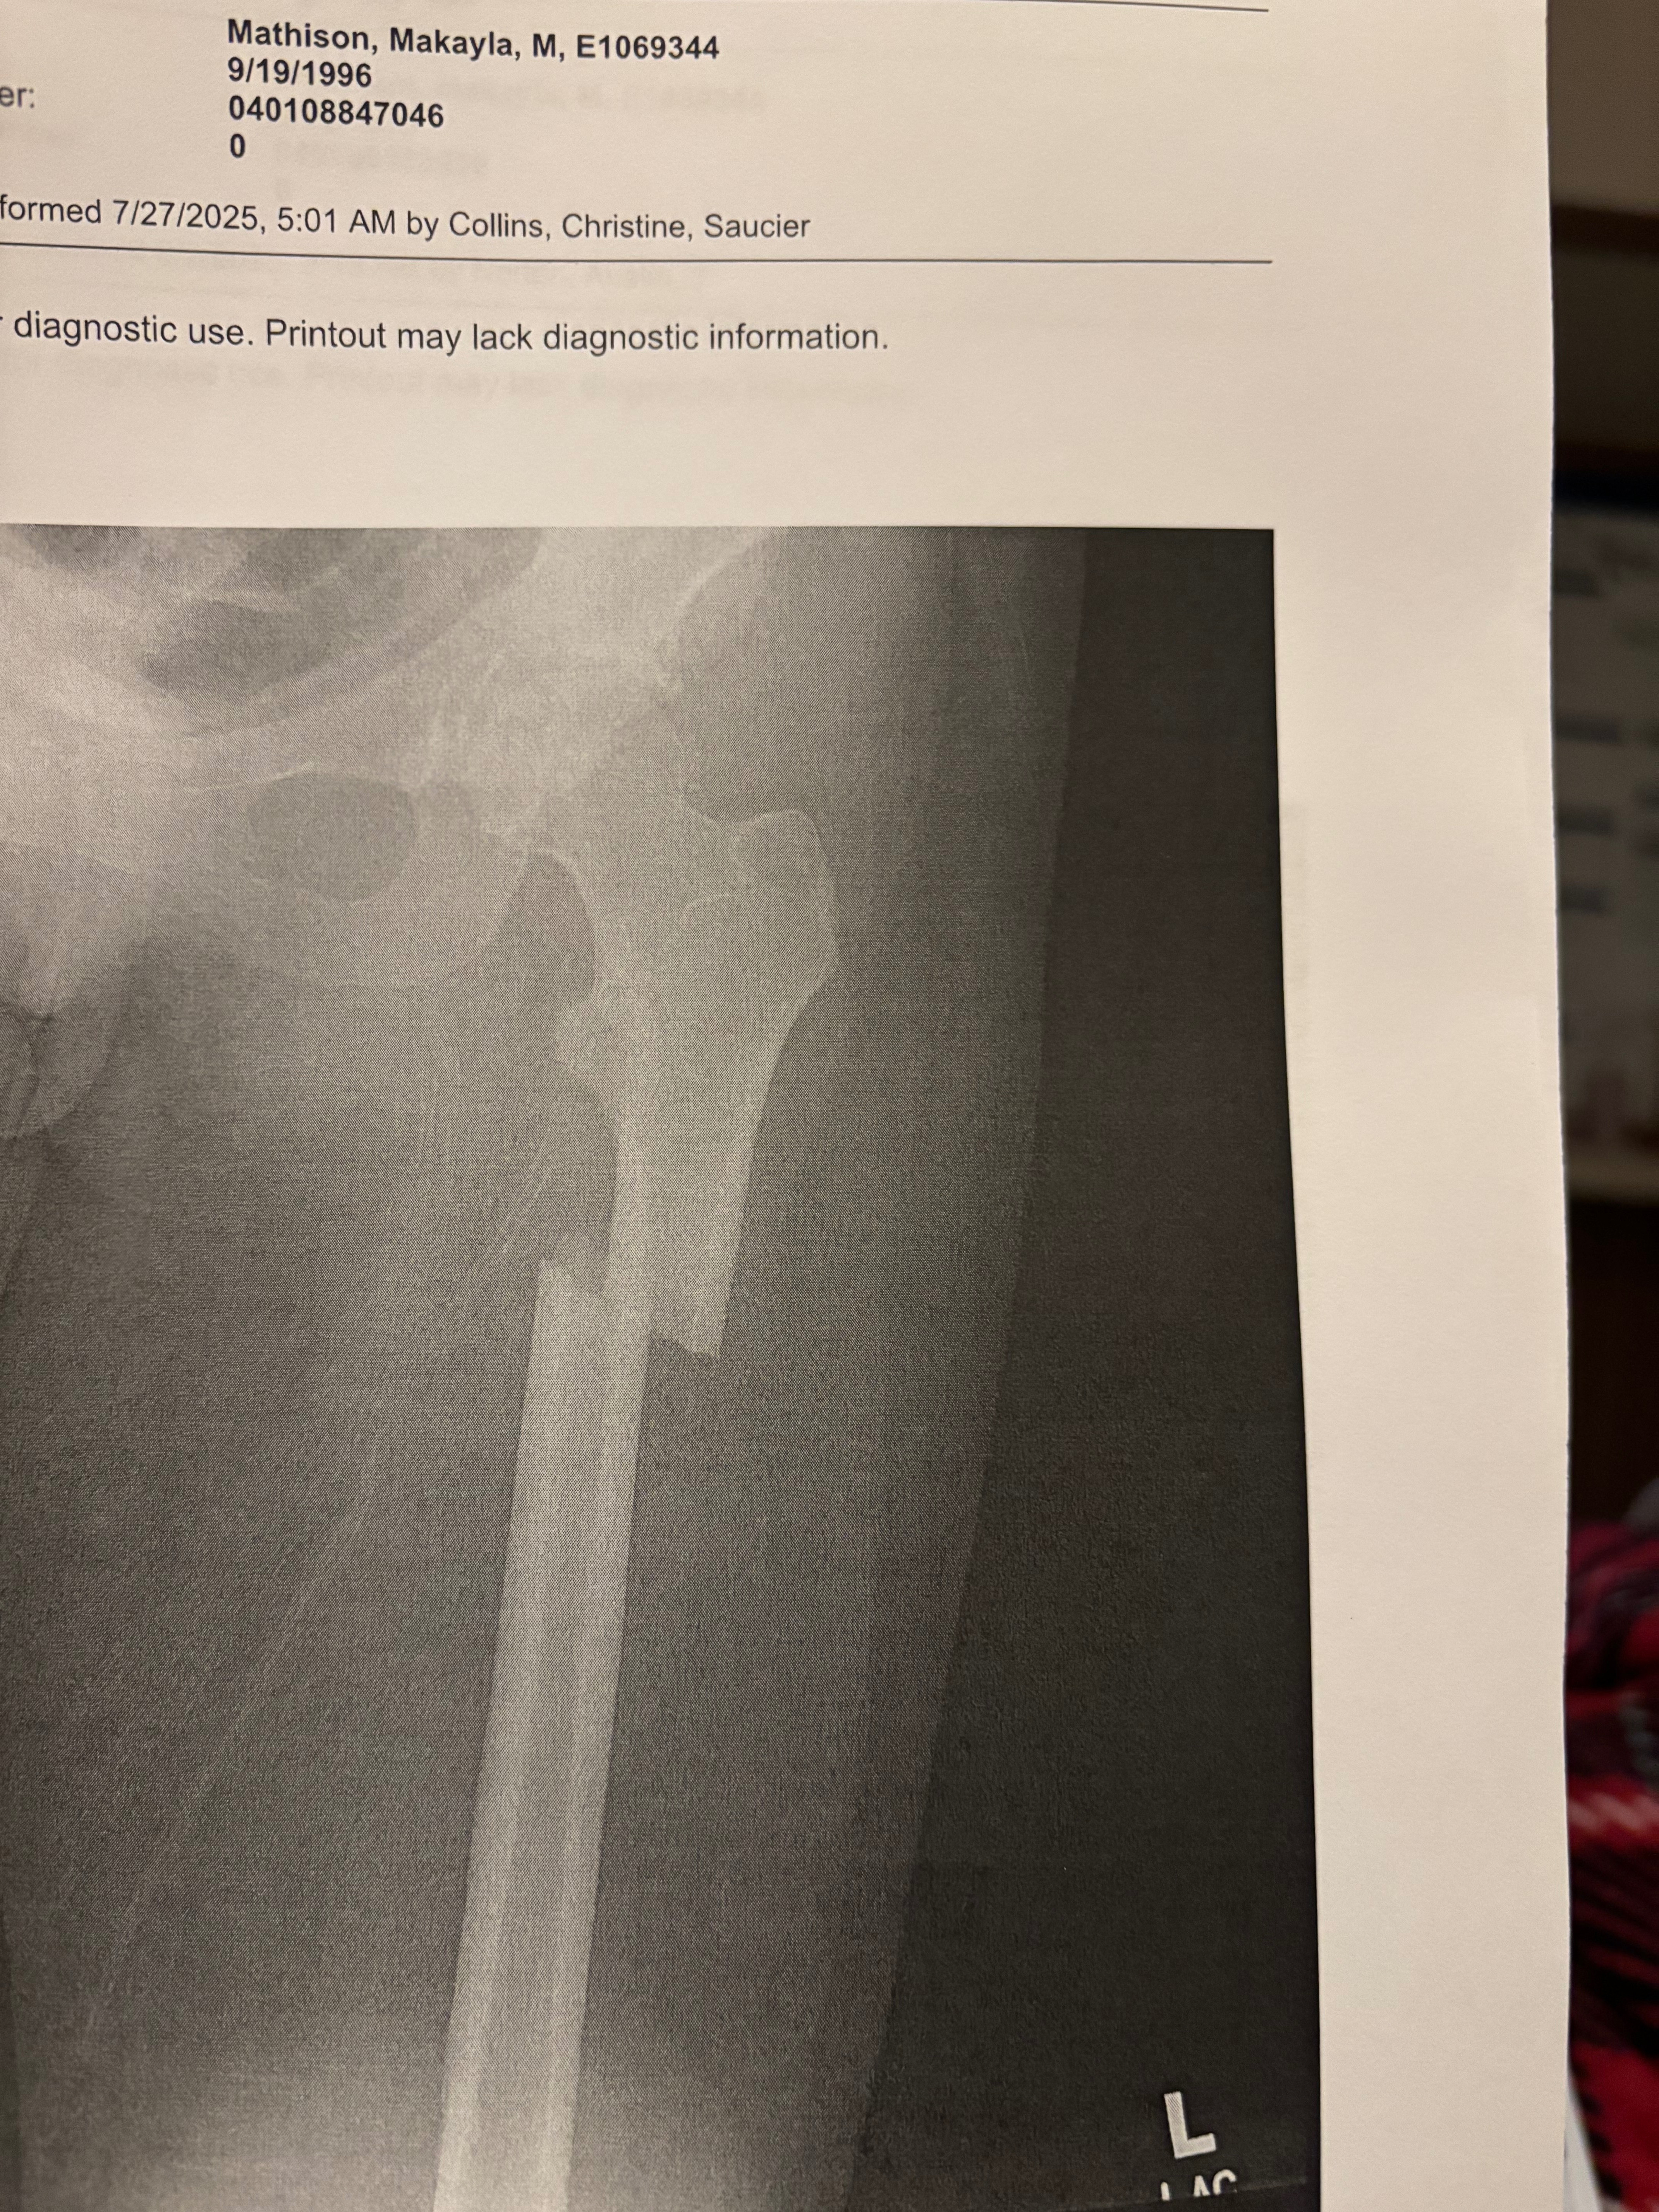

That wasn’t all. My left hip and femur was broken. My sternum was fractured. A large portion of my ribs were shattered. One of my lungs collapsed and had to be partially removed. A chest tube was inserted just so I could breathe.